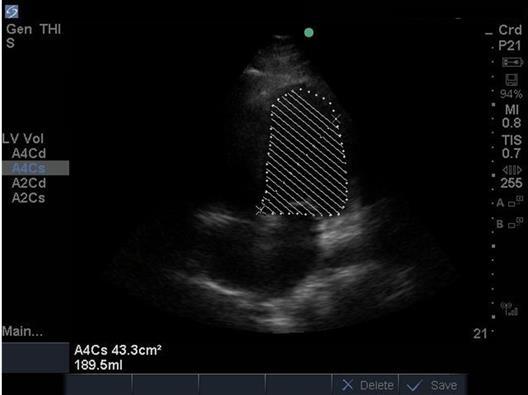

Heart Ejection Fraction (EF) 2 Image